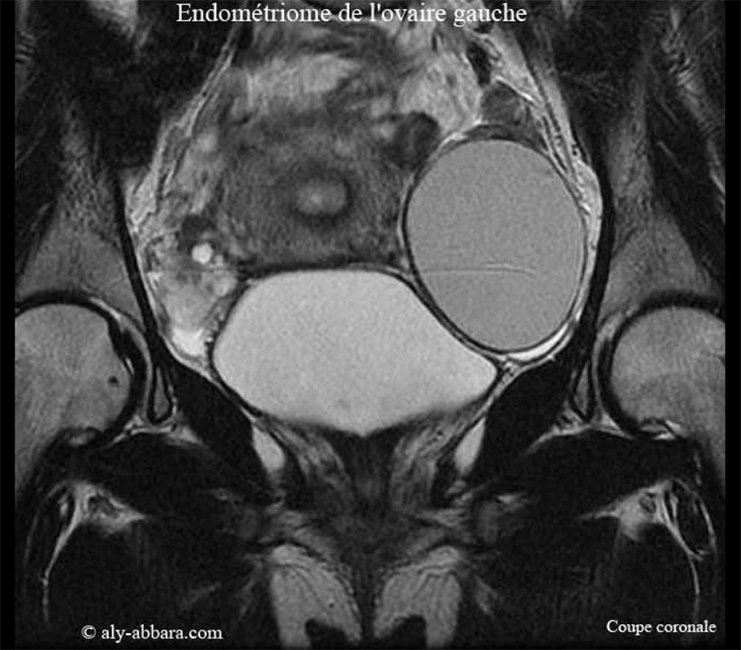

Endométriome de l'ovaire gauche - L'aspect à l'IRM

Endométriome ovarien gauche

• Images échographiques montrant l'aspect IRM (imagerie par résonance magnétique) d'un endométriome (kyste endométriosique) ovarien gauche de 104 cm3 de volume.

Il s'agit d'une formation kystique uniloculaire mesurant (71,7 x 52,5 x 52,6 mm) ; à paroi régulière, de 2 à 3 mm d'épaisseur, avec une seule végétation endophytique (évoluant vers l'intérieur de la cavité kystique) apparaissant sur son endothélium postérieur sous forme de polype de 6 mm de grand axe, pédiculé et ne montrant pas d'activité vasculaire au Doppler.

Le contenu du kyste est liquidien, hypo-échogène faisant penser, soit à un contenu visqueux, mucoïde (kyste mucineux) ; soit au liquide formé du sang lysé, concentré et épaissi, prenant un aspect chocolat

oïde (comme le chocolat fondu), qu'on voit normalement dans les kystes endométriosiques (endométriomes).

Biologiquement les dosages des marqueurs tumoraux sériques chez la patiente sont normaux en dehors d'un taux élevé de CA 125 (76 UI/l ; norme : < 35 UI/L).

Il s'agit d'une femme âgée de 32 ans, mère d'un enfant de 4 ans, ne souffrant d'aucune douleur spontanée ou provoquée, pendant ou en dehors des règles ; elle consulte pour une infertilité secondaire de deux ans ; c'est l'examen clinique qui permet de découvrir la présence de ce kyste.

L'exploration opératoire, et l'examen anatomopathologique confirment la nature histologique de ce kyste ; il s'agit d'un

endométriome isolé (kyste d'endométriose), sans aucune d'autre lésion abdomino-pelvienne ou péritonéale individualisable associée et sans phénomènes adhérentiels intra-abdominal.